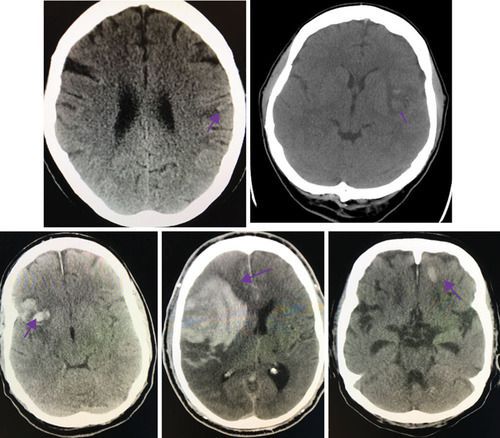

Tissue plasminogen activator is indicated in ischemic stroke. However, there are few absolute contraindications of tPA therapy in stroke patients. These contraindications are: - Intracranial hemorrhage - Suspicion of subarachnoid hemorrhage - Head trauma or any neurosurgery in past 3 months - Uncontrolled hypertension - Arteriovenous malformations - Active bleeding - Endocarditis - History of intracranial hemorrhage Reference: https://www.mdcalc.com/tpa-contraindications-ischemic-stroke Image via: https://www.ahajournals.org/doi/full/10.1161/str.0000000000000152